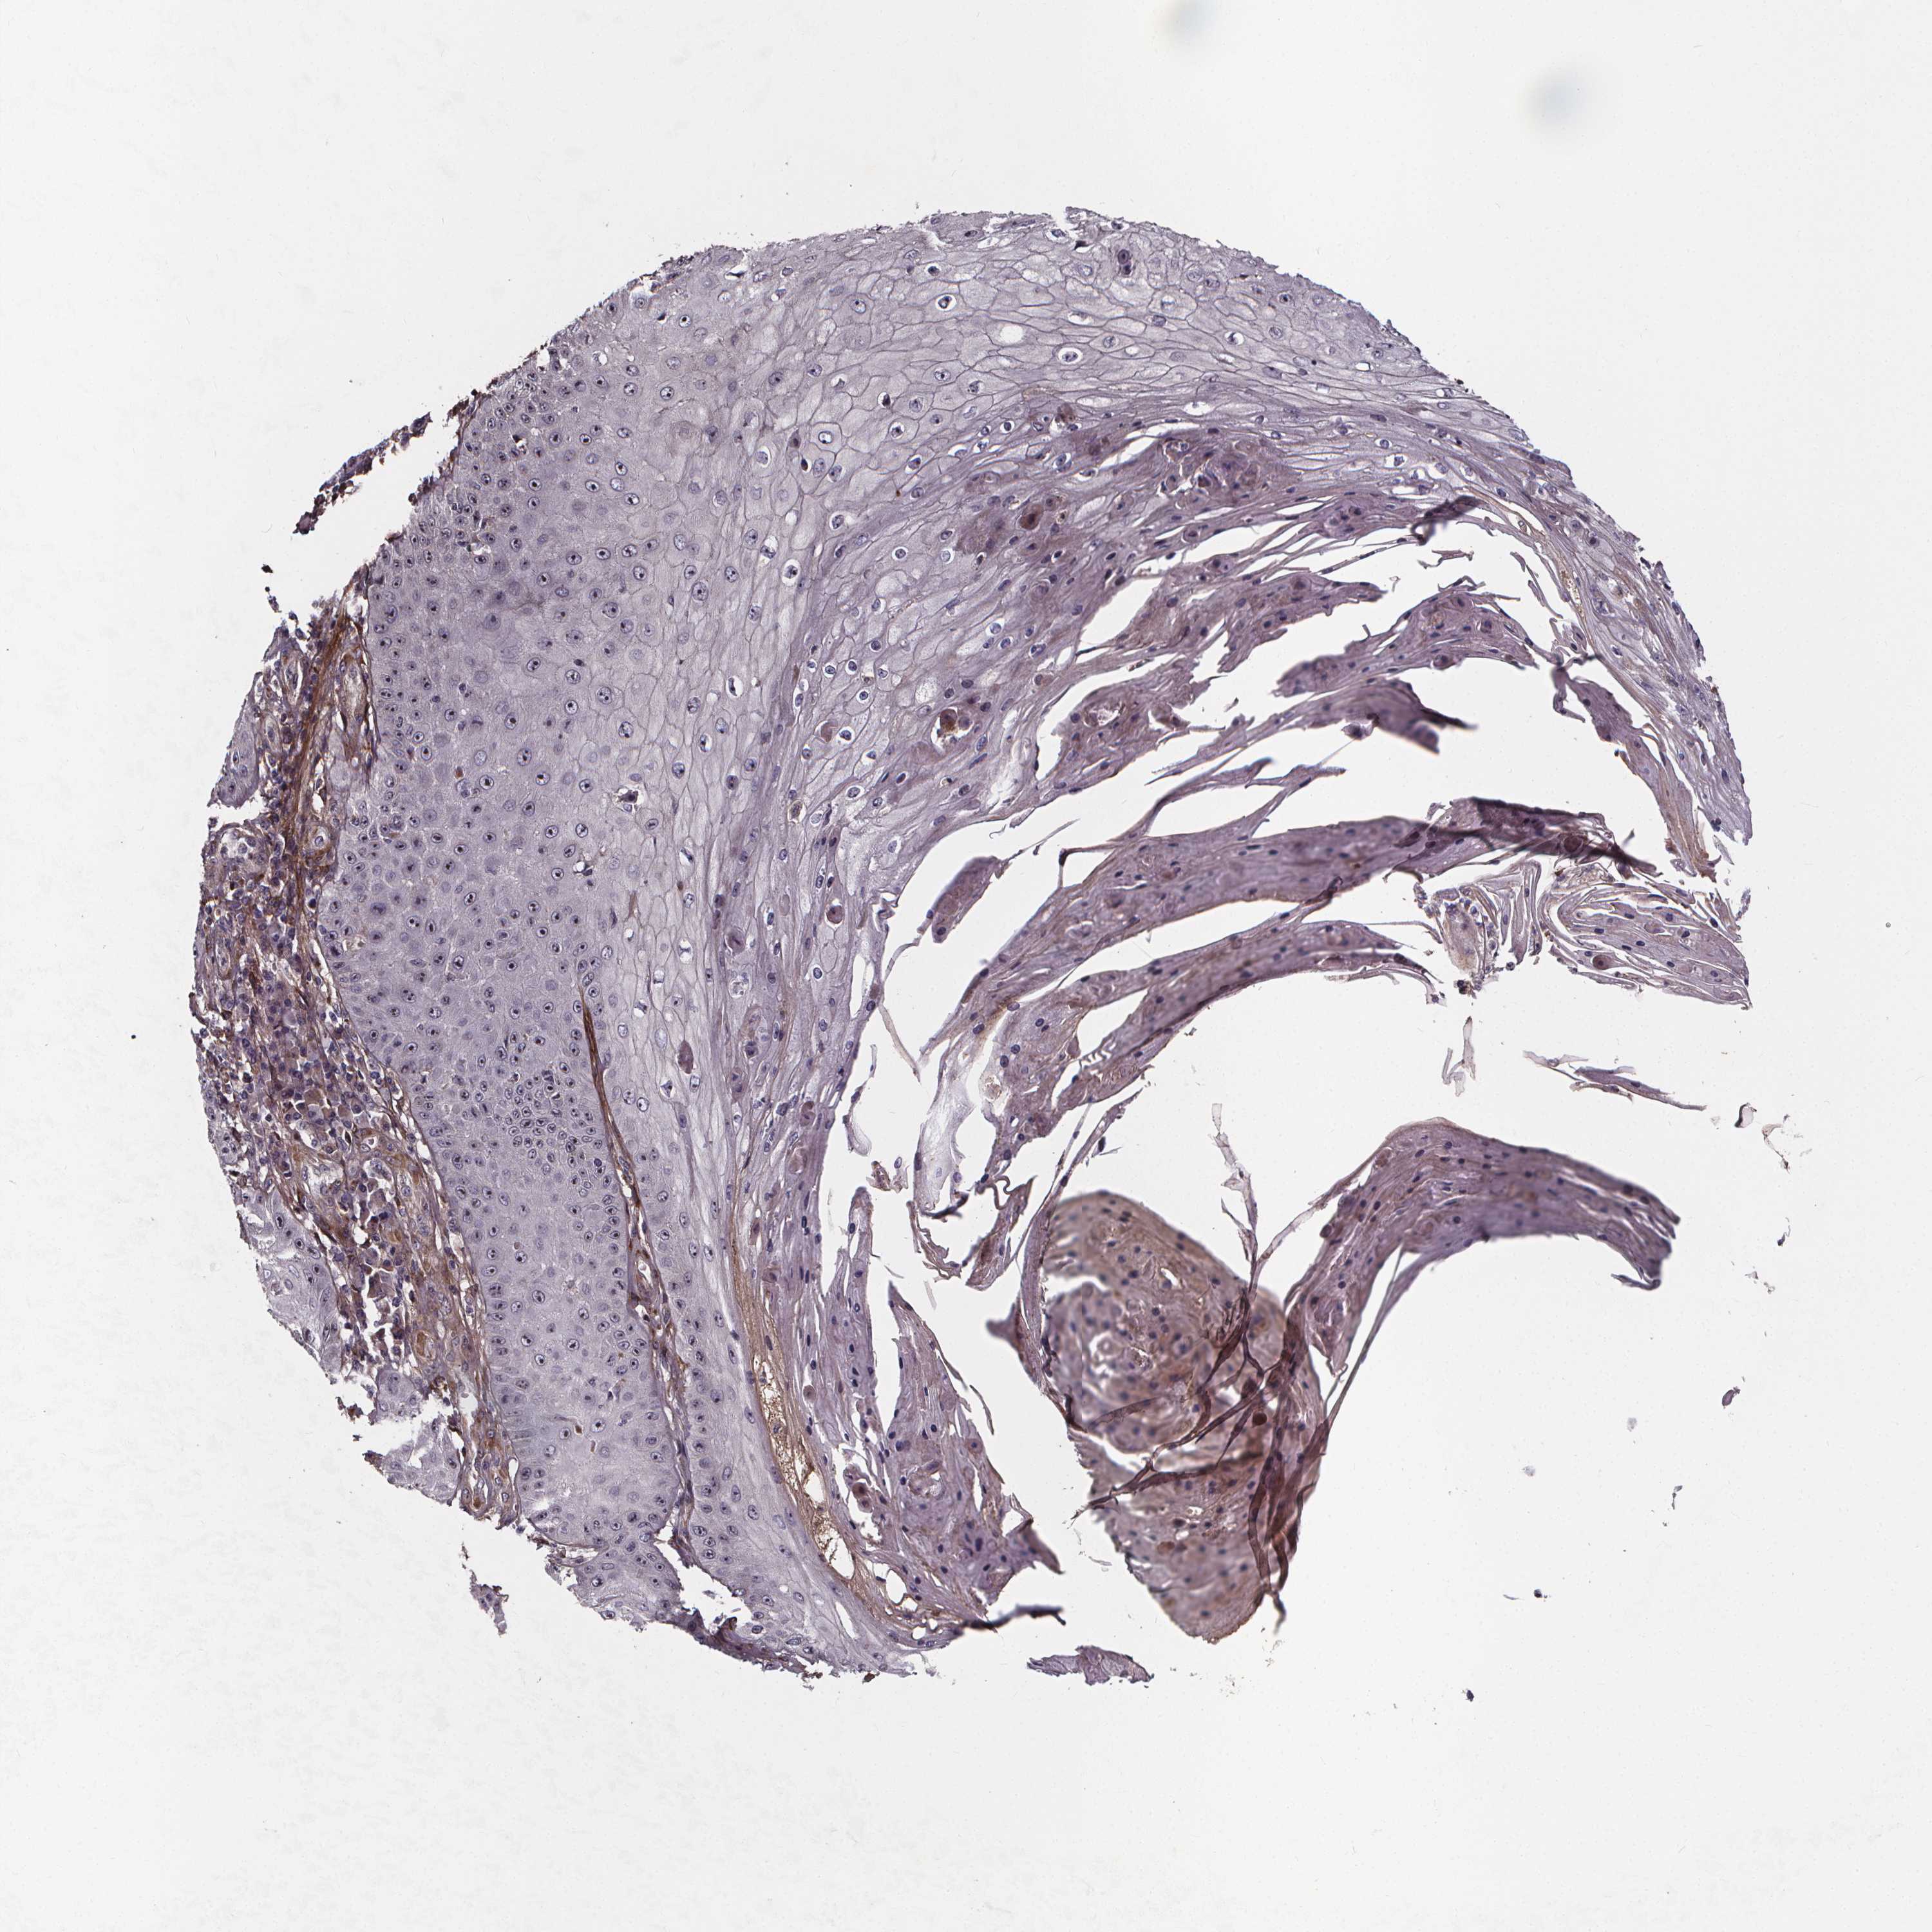

CANCER SKIN CANCER Show tissue menu

Basal cell and squamous cell cancer

SKIN CANCER - Protein expressioni

A mouse-over function shows sample information and annotation data. Click on an image to view it in a full screen mode. Samples can be filtered based on level of antibody staining by selecting one or several of the following categories: high, medium, low and not detected. The assay and annotation is described here.

Each image is clickable and will lead to virtual microscopy that enables deeper exploration of all samples and also displays staining intensity scores, fraction scores and subcellular localization as well as patient and tissue information for each sample.

Antibody HPA064970

Squamous cell carcinoma, NOS